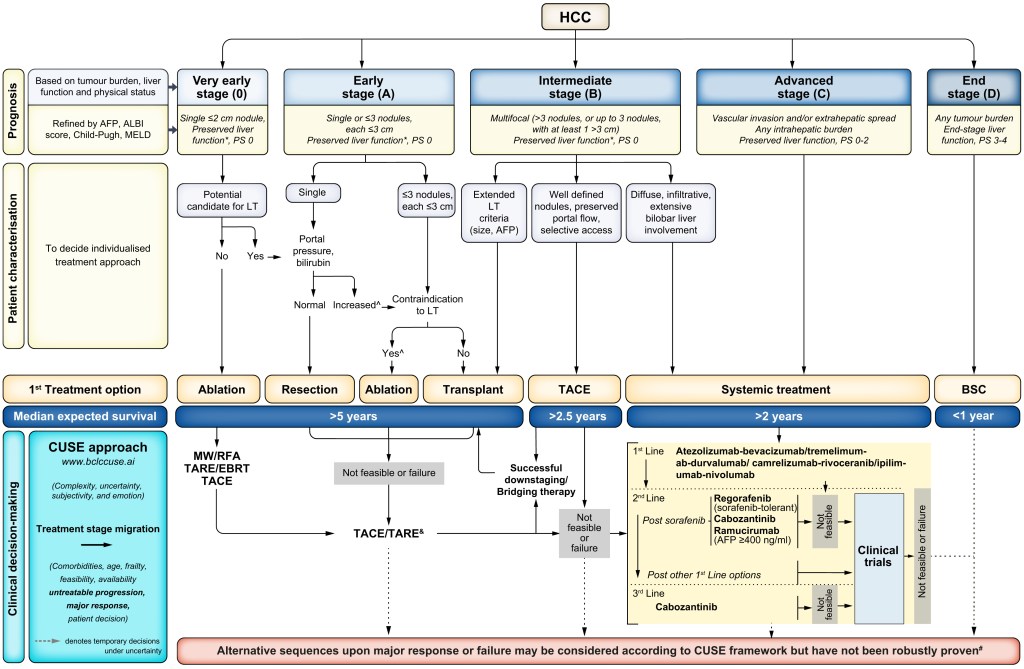

Para um hepatocarcinoma precoce (tumor único até 5 cm ou 3 tumores não maiores que 3 cm, sem comprometimento de vasos e sem metástases), há duas principais opções de tratamento. A melhor opção, apesar de muito agressiva, ainda é o transplante do fígado, onde o órgão doente é substituído por outro sadio. Outra opção é a hepatectomia, cirurgia onde é retirada a porção do fígado onde está localizado o tumor. Ambas as cirurgias são consideradas curativas do câncer se realizadas a tempo, mas na hepatectomia o fígado continua com cirrose e a possibilidade de surgir um novo câncer continua.

Quando o tumor é grande demais para ser considerada a possibilidade de transplante ou cirurgia, existe a possibilidade de reduzir o seu tamanho através de quimioembolização (TACE), que é um procedimento onde o radiologista intervencionista identifica a artéria que está nutrindo o tumor, injeta uma dose de quimioterápico direto na lesão e entope a artéria para “matar” o câncer. Apesar de ser considerado um tratamento paliativo ou como “ponte” para o transplante, também pode curar. Uma variação mais recente desse tratamento, que cada vez fazemos mais, é a radioembolização, onde ao invés de um quimioterápico injetamos microesferas radioativas.

Outra opção cada vez mais utilizada é o tratamento percutâneo (pela pele) do tumor. Essa modalidade terapêutica se popularizou com a técnica japonesa de injeção percutânea de etanol (PEI). Esse era um método simples e eficaz, realizado sob anestesia local e com raras complicações. Com o auxílio do ultrassom, é introduzida uma agulha no centro do tumor, através da pele, onde é administrado álcool absoluto (a 100%), provocando a destruição da lesão. Infelizmente, como é um procedimento simples e barato, sem necessidade de equipamentos de última geração ou de medicamentos de alto custo, a técnica foi abandonada das pesquisas clínicas de tal modo que não conseguimos nem comparar com os novos métodos de tratamento, sendo excluída das diretrizes internacionais.

Da injeção percutânea surgiram outros métodos semelhantes, chamados de ablação, onde uma agulha também é introduzida acompanhada por ultrassom ou tomografia, mas nada é injetado. Ao invés disso, a agulha emite microondas ou radiofrequência e “cozinha” o tumor.

Quando o hepatocarcinoma é muito grande, são muitas lesões ou a doença do fígado ou as condições do paciente não permitem os tratamentos anteriores, ainda restam os tratamentos sistêmicos (quimioterapia). Historicamente, sabemos que o hepatocarcinoma não responde bem a quimioterápicos convencionais, o que faz um certo sentido, já que os hepatócitos em si já evoluíram para lidar com todo tipo de veneno que nós e nossos ancestrais entraram em contato. Além disso, mesmo se quisermos usar medicamentos mais tóxicos, trata-se de pessoas com fígado doente, com pouca reserva funcional e o tratamento pioraria ainda mais a situação. Assim, descobrimos que ao invés de tentar destruir diretamente o hepatócito mutante e “superpoderoso”, temos que usar de subterfúgios como retirar o suprimento de sangue e ajudar o sistema imunológico.

Hoje temos diversos tipos diferentes de quimioterápicos para o hepatocarcinoma. Os inibidores da tirosinoquinase (sorafenibe, lenvatinibe, regorafenibe e cabozantinibe) foram considerados até hoje a primeira linha de tratamento sistêmico, mas com resultados não muito animadores. Os imunobiológicos, que agem em pontos mais específicos, tendem a ser melhor tolerados e ter melhor resposta, deixando de ser usados isoladamente para agora ser indicados em duplas.

A dupla “atezo-bevo” (atezolizumabe com bevacizumabe) pode hoje ser utilizada como primeira linha no tratamento sistêmico, mas está contraindicada em pacientes com varizes esofágicas não tratadas pelo alto risco de hemorragia. Outra combinação potente que compete pelo status de primeira linha é tremelimumabe com durvalumabe.

A escolha do tratamento do hepatocarcinoma depende então muito do estágio em que ele é diagnosticado, mas também das condições do fígado, da causa da cirrose e da experiência e disponibilidade no serviço com as diversas modalidades terapêuticas. Um radiologista intervencionista mais habilidoso pode favorecer procedimentos invasivos em um lugar, um ótimo cirurgião pode ter melhores resultados em outro, num terceiro a falta de grupo bem treinado de transplante hepático pode favorecer técnicas ditas como não curativas.